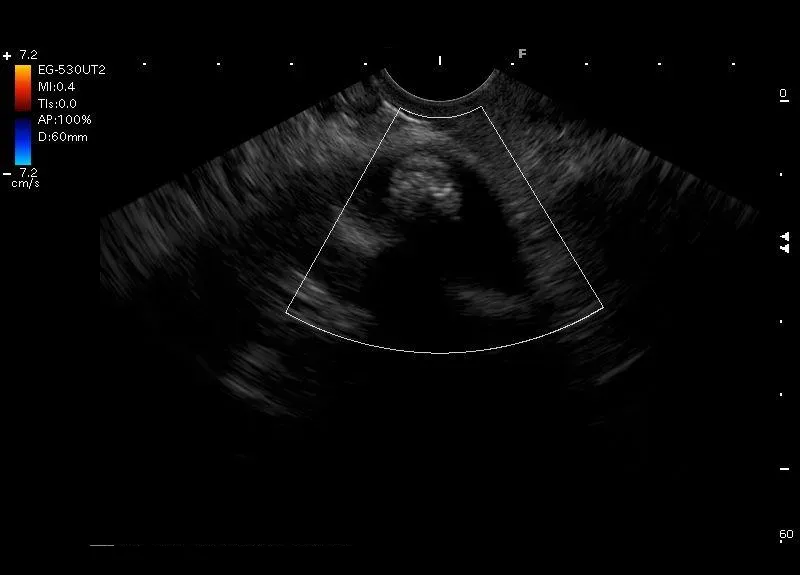

Hiperechogeniczna zmiana z cieniem akustycznym, bez przepływu naczyniowego w opcji Doppler, widoczna w świetle obkurczonego na niej pęcherzyka żółciowego - złóg w pęcherzyku żółciowym